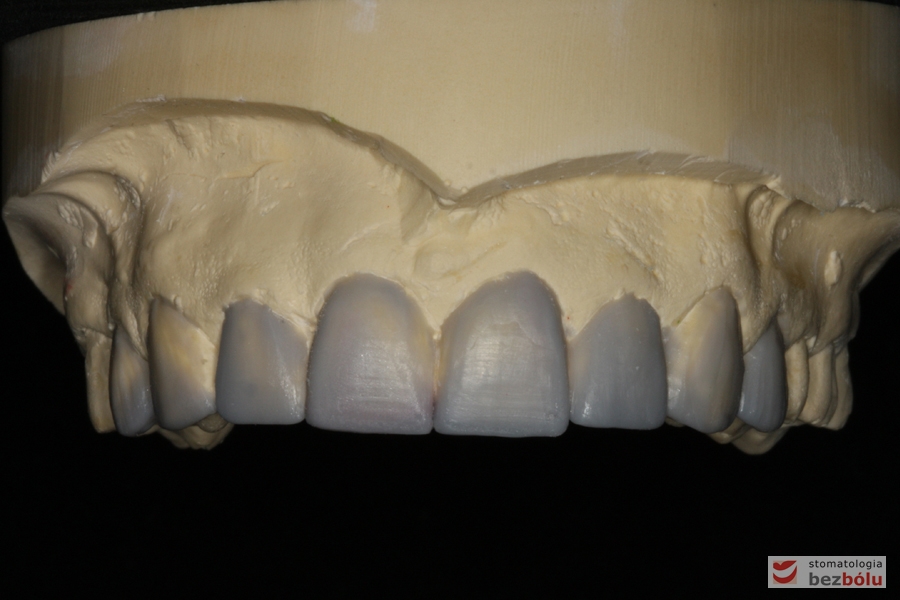

Wizualizacja docelowej odbudowy protetycznej - wax-up

Wizualizacja docelowej odbudowy protetycznej – wax-up